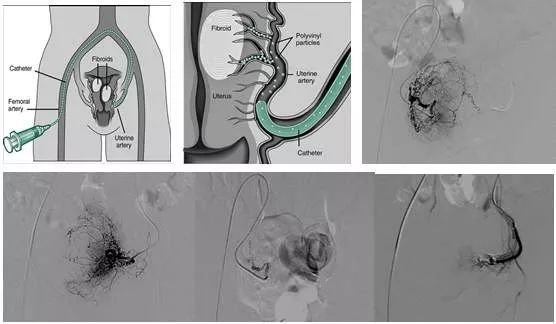

子宫肌瘤介入治疗原理

在腹股沟韧带中点下0.5厘米处触及股动脉博动最强处作为穿刺点,经导管推注一定大小,一定量的栓塞颗粒将子宫肌瘤供血血管及正常子宫动脉分支的一定末梢血管栓塞。

(1)可以直接切断子宫肌瘤的血液供应,瘤体缺血坏死,逐渐萎缩变小,并改善由于肌瘤占位所引起的压迫症状。

(2)子宫肌瘤具有性激素依赖性,雌激素能促进肌瘤生长。切断肌瘤供血能阻雌激素经血流进入肌瘤内,瘤体雌激素水平显著下降,局部形成一个类似绝经期的激素内环境,肌瘤进一步萎缩。

(3)子宫动脉栓塞后,子宫血供显著下降,子宫内膜生长受到抑制月经量减少,经期恢复正常。贫血逐渐得到改善和恢复。